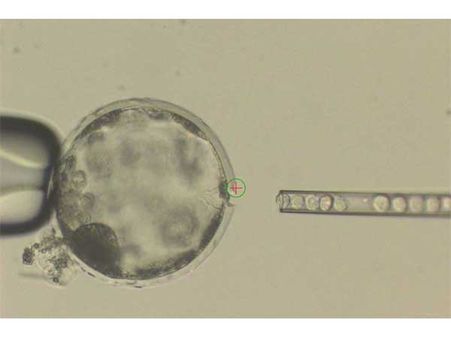

This hybrid is a pig embryo that is injected with human cells. Scientists have announced that they have been successful in creating the very first functioning human-animal hybrid! This project proves that human cells have the ability to be introduced into a non-human being as well, and it can survive and grow in those conditions. In this case, they've used it on a pig.

One of the ways to build a chimera is by introducing one animal's cells into another animal's embryo. After this, it is let to grow into a hybrid.